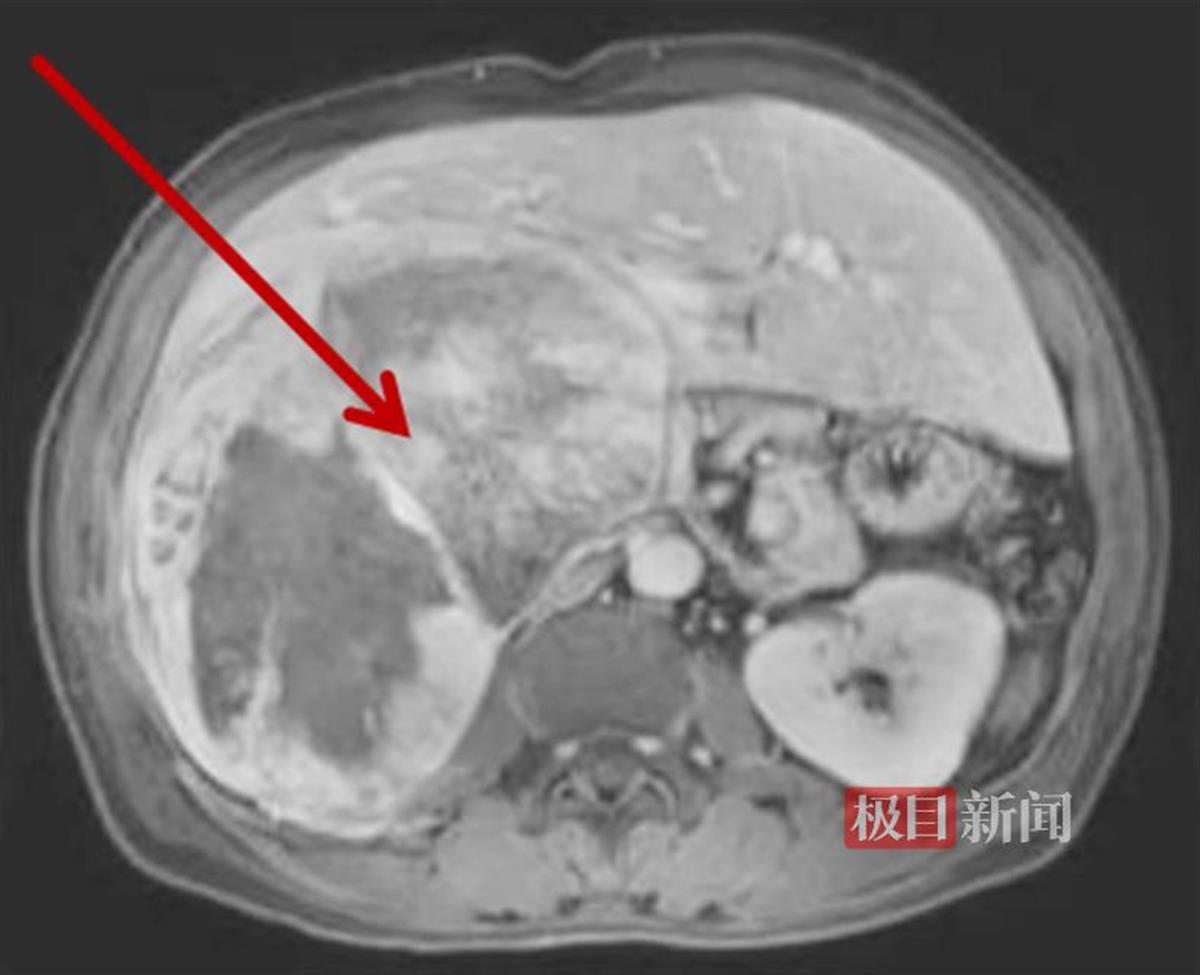

术前影像检查发现肝脏巨大肿瘤

术后一周复查,残肝体积增生